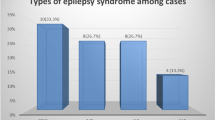

The clinical characteristics of ECTS patients and controls were presented in Table 1. The PSI of ECTS patients was significantly decreased than controls (P = 0.04), and no significant differences in VCI (P = 0.70), PRI (P = 0.32), WMI (P = 0.94), and FSIQ (P = 0.26) were found between ECTS patients and healthy controls. In multivariate linear regression analysis, age at seizure onset was the only significant factor for VCI (P = 0.001), PSI (P = 0.015), and FSIQ (P = 0.002) (Fig. 2).

In patients with ECTS, 39.3% (n = 11) of patients underwent monotherapy, and 35.7% (n = 10) underwent polytherapy. The most frequently used AED was oxcarbazepine (OXC, n = 13), followed by levetiracetam (LEV, n = 12), valproate (VPA, n = 5), and lamotrigine (LTG, n = 1) (Table 2). The seizure duration (P = 0.763), time of AED treatment (P = 0.555), and AED treatment types showed no significant influence (P = 0.789) on PSI.